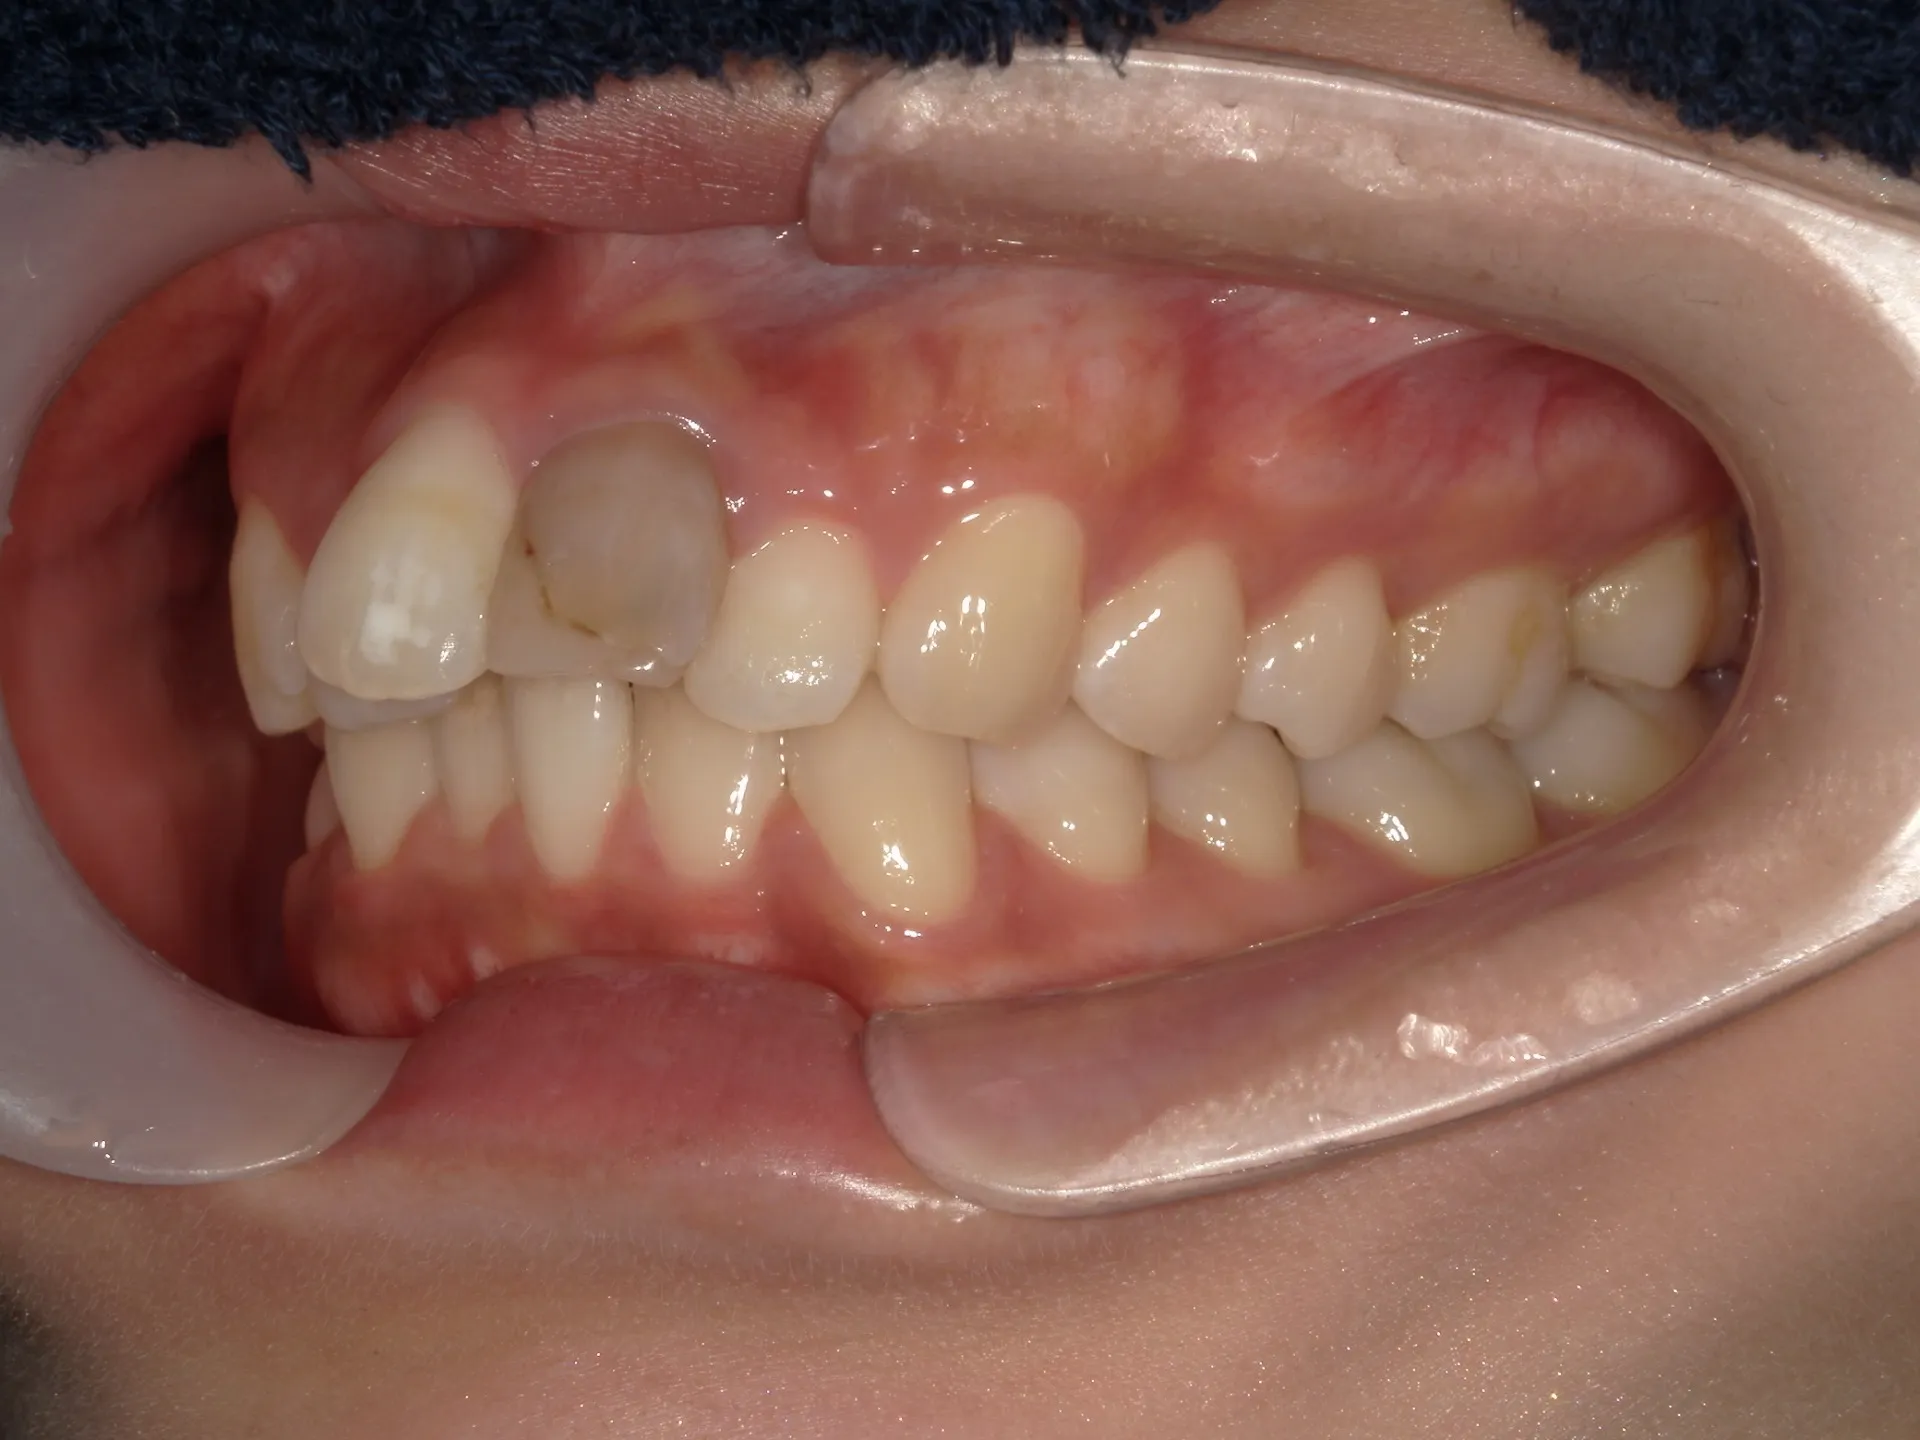

大きく飛び出してしまった前歯の矯正と変色の治療を希望された症例をご紹介いたします。